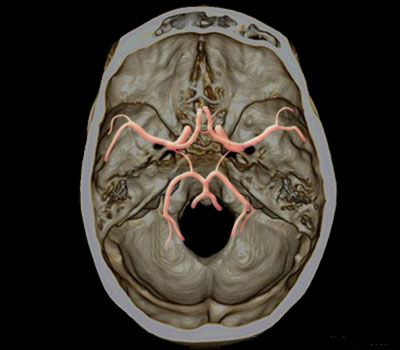

Polygone de Willis